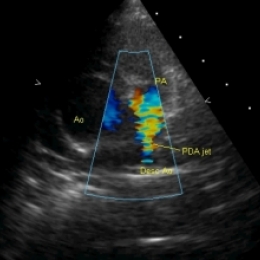

Баталов проток - что это такое и зачем он должен зарастать?

Открытый Баталов проток — это заболевание сердца, которое появляется у детей вскоре после рождения. С помощью Баталова протока соединяются два главных сосуда, отходящих от сердца, - лёгочная артерия и аорта. В утробе эти сосуды должны быть соединены, так кровь не должна поступать в неработающие лёгкие плода. Кислород она получает от матери,и поэтому кровь поступает из лёгочной артерии в аорту, минуя лёгкие. В норме в течение нескольких минут — нескольких дней после рождения Баталов (артериальный) проток закрывается. У некоторых детей он остаётся открытым, тогда артериальная кровь в аорте, богатая кислородом, будет смешиваться с венозной кровью, бедной кислородом. Это приведёт к нарушению снабжения органов и тканей кислородом, а вследствие этого к нарушению их функционирования.

Эхокардиография (Эхо-КГ) — это безболезненное обследование сердца при помощи ультразвука, оно позволяет увидеть строение и работу сердца вашего ребёнка. Прибор выводит изображение на экран, как и при УЗИ органов брюшной полости или малого таза, затем делается несколько снимков и пишется заключение врача УЗ-диагностики. При помощи этого обследования можно обнаружить открытый Баталов проток и оценить изменения, которые могут возникнуть сердце при данном пороке (увеличение камер сердца, при отсутствии лечения основного заболевания, как правило, приводящее к сердечной недостаточности).